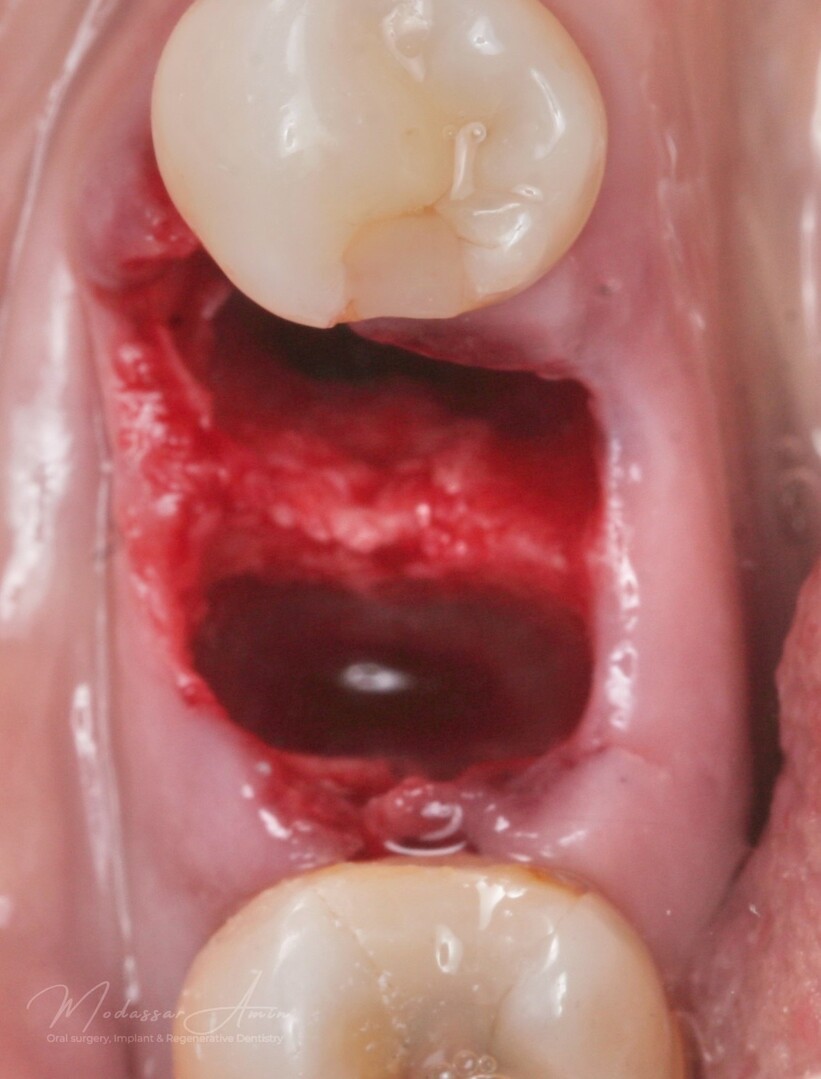

Pasienten presenterte med tann 46 som ikke kunne bevares grunnet en dyptgående infraksjon inn i furkasjonen. Forholdene lå til rette for en immediate implantatbehandling. Ved hjelp av Versah osseodensifikasjonsbor ble det interradikulære beinet ekspandert på en skånsom og forutsigbar måte, noe som ga høy primærstabilitet (>40 Ncm) til tross for en lokal bendefekt apikalt mesialt etter kronisk apikal periodontitt. Den gode stabiliteten muliggjorde bruk av SSA (Sealing Socket Abutment) for forsegling. På grunn av tynn bløtvevsfenotype bukkalt ble behandlingen supplert med bindevevstransplantat (CTG):

Minimal invasiv ekstraksjon